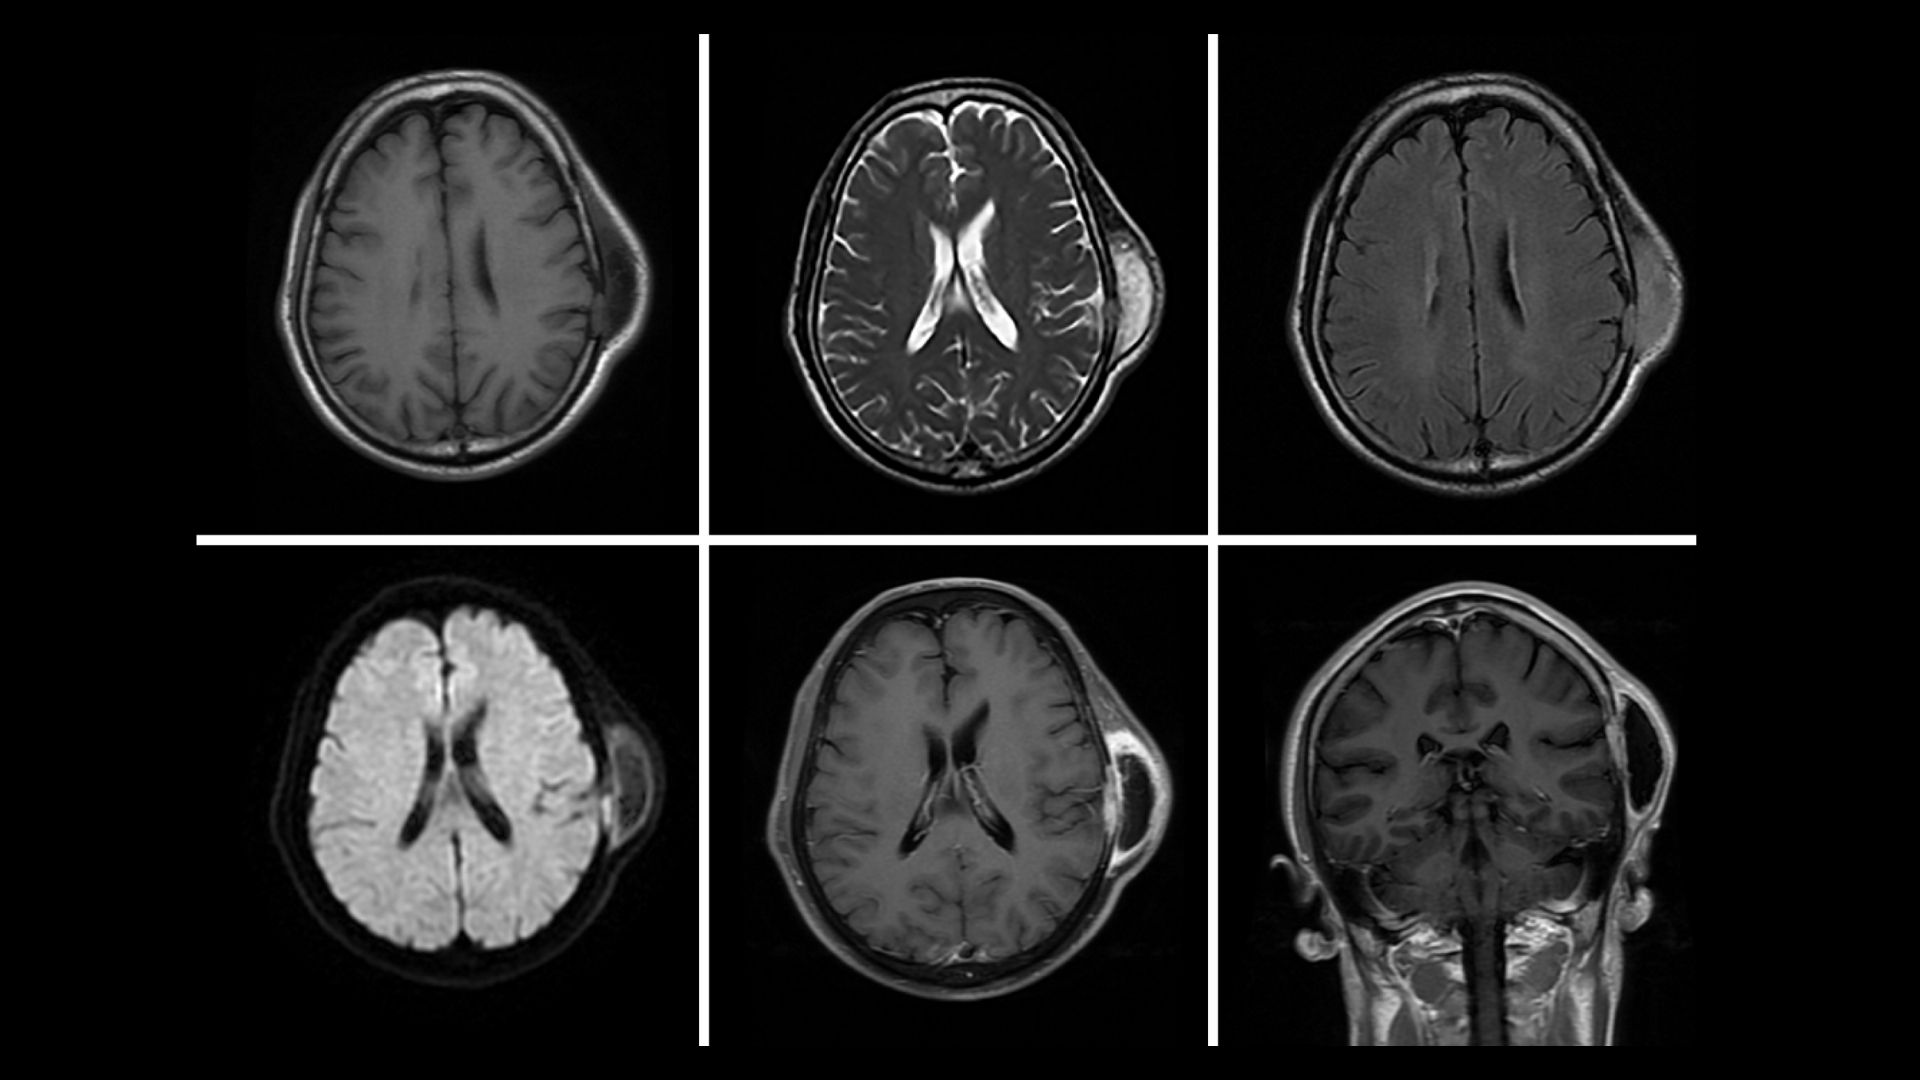

Early detection is critical to improving prognosis and treatment outcomes. Regular screenings, such as ultrasound or MRI scans, particularly for genetically predisposed groups, support early-stage diagnosis where treatment efficacy significantly increases. AllCancer’s “Cure First, Pay Later” policy emphasizes timely patient-centric screening, ensuring financial strains never compromise the prompt detection and comprehensive management of diseases like Rhabdomyosarcoma.

• Advanced Diagnostics: State-of-the-art imaging (e.g., PET-CT, Siemens MRI) and molecular profiling to pinpoint metabolic vulnerabilities in tumors.

• Medical Records: Recent diagnostic reports, imaging scans (e.g., CT, MRI, PET-CT), pathology results, and treatment history. Digital or physical copies are accepted.